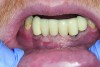

The presence of keratinized tissue around teeth and implants and its role in periodontal maintenance is somewhat controversial. It has been suggested that 2 mm of keratinized tissue is important to maintain gingival health around teeth.16 Minimal recession also facilitates maintenance by the therapist and plaque control by the patient (Figure 4 and Figure 5). Keratinized tissue around implants is also important. Chung et al17 completed a retrospective study examining the barrier function of keratinized tissue around dental implants. They examined 339 endosseous dental implants in place for at least 3 years in 69 patients and found that when an adequate band of keratinized tissue was present, less inflammation and plaque accumulation occurred (Figure 6 and Figure 7). Although there was no correlation to bone loss, there was improved comfort while cleaning the sites with keratinized tissue versus those areas that lacked keratinized tissue.

Fig 6. View of implant-supported restoration—the center implant had gingival augmentation prior to the loss of the tooth.

Figure 6

Fig 7. Close-up view of the No. 23 implant-supported restoration showing inflammation surrounding the site (this area had not been grafted).

Figure 7